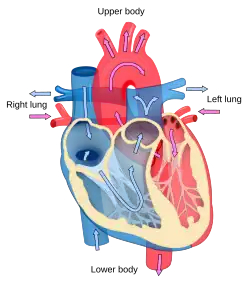

Blood flow diagram of the human heart. Blue components indicate de-oxygenated blood pathways and red components indicate oxygenated blood pathways. | |

The primary responsibility of the heart is to pump blood throughout the body. It pumps blood from the body — called the systemic circulation — through the lungs — called the pulmonary circulation — and then back out to the body. This means that the heart is connected to and affects the entirety of the body. Simplified, the heart is a circuit of the circulation.[20] While plenty is known about the healthy heart, the bulk of study in cardiology is in disorders of the heart and restoration, and where possible, of function.